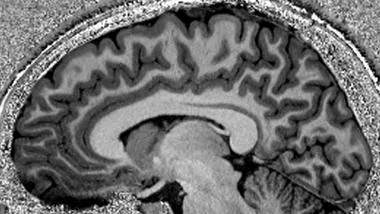

Lecturer in Magnetic Resonance Physics

Pete Lally is a Lecturer in Magnetic Resonance Physics and honorary member of staff at the School of Biomedical Engineering & Imaging Sciences, King's College London.